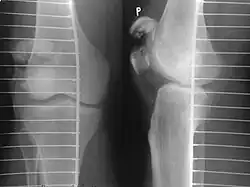

Patella fracture

| Other names: Broken kneecap | |

| A fracture of the patella seen on a lateral view | |